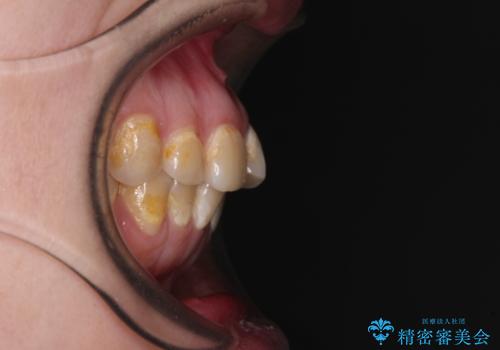

上顎側切歯(上の真ん中から2番目の歯)が舌側転位している場合、無理して動かそうとすると歯髄壊死を起こすリスクが高い印象があります。

インビザライン単体でも治療は可能ですが、安全策としてインビザラインで歯列を移動する前に上顎前歯をワイヤー矯正で整え、その後上下歯列をインビザラインにて矯正治療を行うこととしました。

舌側転位している側切歯特有の、切縁の位置が不揃いであったり、根元が内側に引っ込んだ状態であったりという、インビザライン独特の仕上がりになることなく、きれいに整った歯列とすることができました。